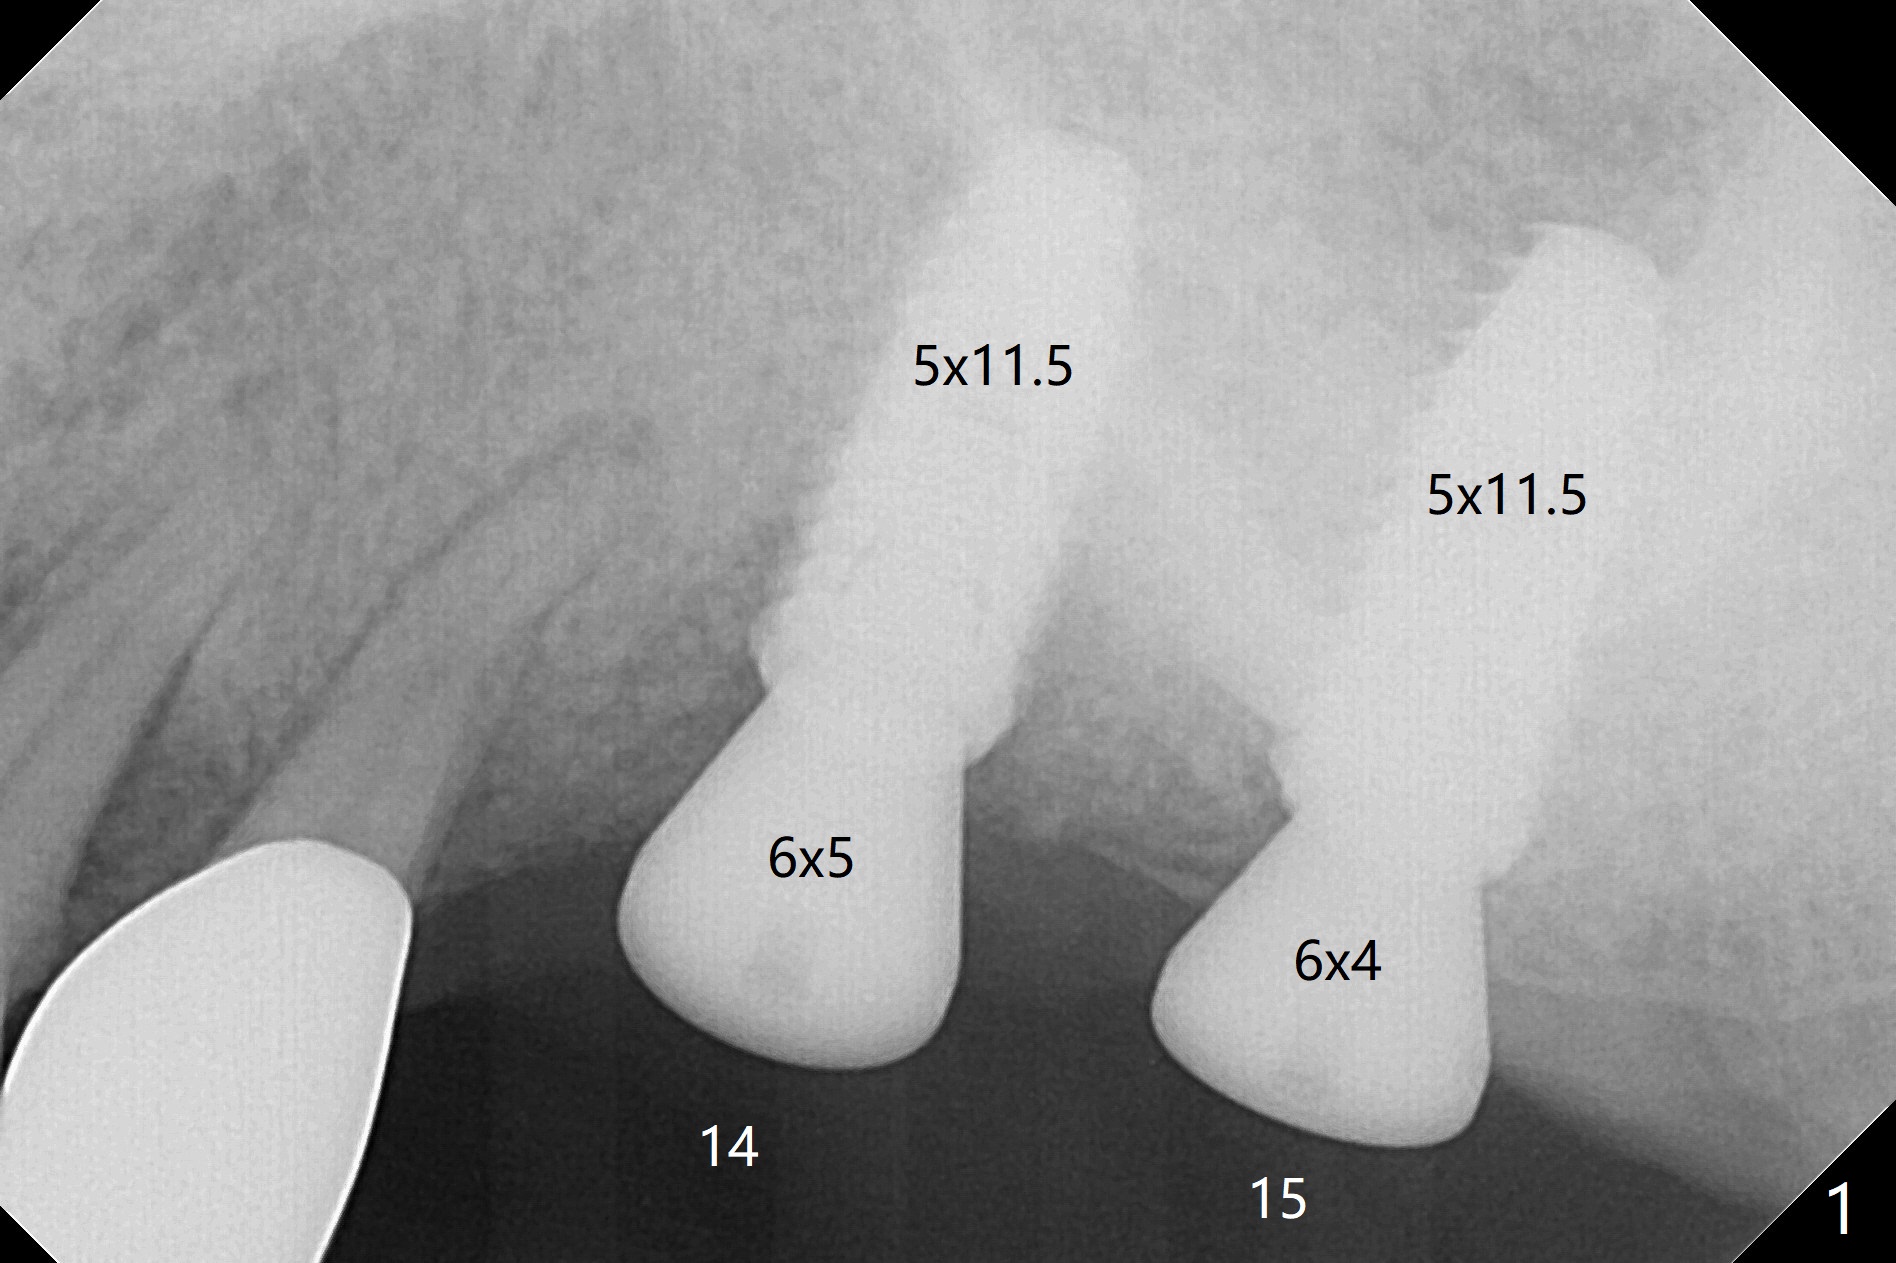

Implants than Designed

At the time of surgery, there are no 5x10 mm implants in the office for the sites of #14 and 15. Reanalysis of CT shows that there is enough bone for 11.5 mm implants. Before implant placement (Fig.1), there is no perforation of the sinus floor, as shown by probing and nasal blowing test. When a 3.5x11.5 mm implant is placed at #29 in the same appointment, it appears to be supracrestal buccal. Autogenous bone (Fig.2,3 *) is placed in the osteotomy following insertion of a healing screw (S). Periodontal dressing is applied, but it is dislodged after dinner. In fact there is bone coronal to the implant 4.5 months postop (Fig.4), which is confirmed during uncover procedure. There is no abnormality at #14 or 15 4.5 months postop (Fig.5). Impression is taken following extraction of the abnormally shifted opposing tooth #18.